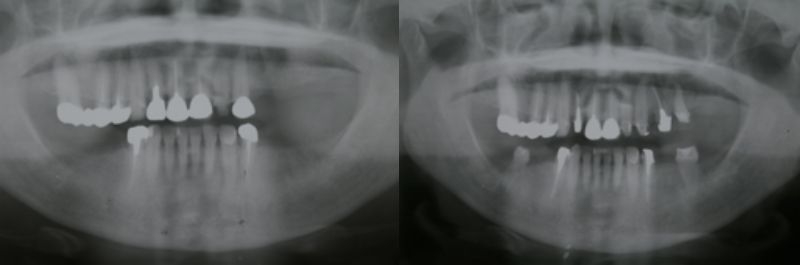

下の画像はレントゲン写真になります。レントゲンの見方ですが、向かって左がその患者さんの右になります。ちょうど向かい合わせになっていると思ってください。硬いところ(金属、歯、骨)は白く映り、柔らかいところ(歯肉、頬、唇)はほとんど黒くなって映りません。(根の中の白いのは硬いものではなくバリウムの様な造影剤が入っています

この患者さんは左上が4本なく、左右の下は3本ずつ合計で6本歯がありませんでした。そのため上下で入れ歯を入れていました。

娘さんが矯正治療で歯を4本抜くことになった為、その4本をお母さん(この患者さん)に植えることにしました。

■症例(術後)

右の画像は娘さんの歯を4本植えたところです。左上に2本、左右の下に1本ずつ植えています。その為入れ歯がなくても噛めるようになりました。しかし下は約5年しか使えませんでした。免疫反応で体が要らないものだと、吸収してしまうのです。上は10年以上使えています。